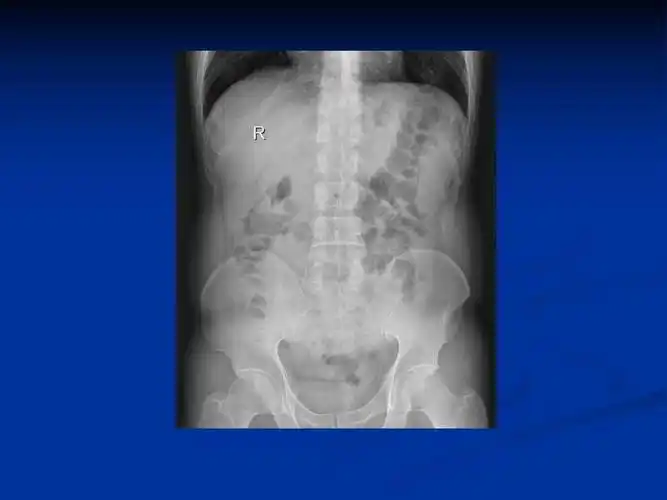

肠梗阻x线图片

一位典型肠梗阻患者的x线平片,可以看到明显的扩张积气肠管.

腹部x光片显示肠梗阻

典型的肠梗阻表现